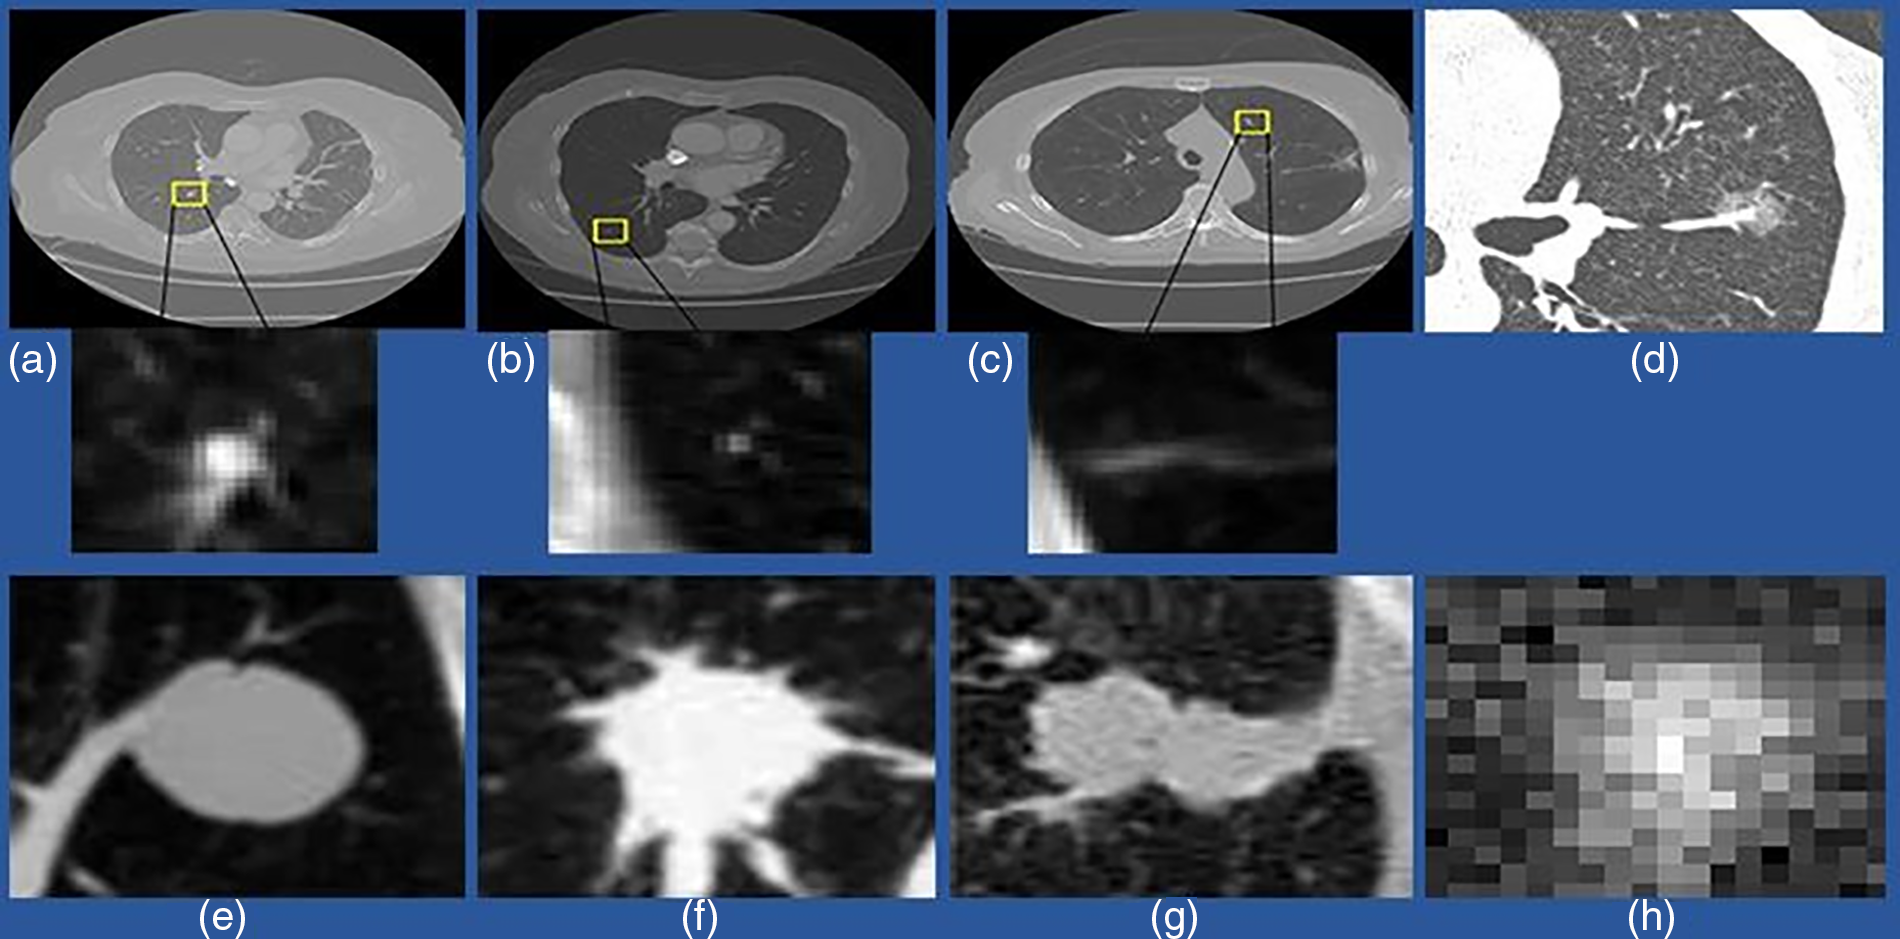

Generally, pulmonary nodules are small, rounded, or geometric shapes with approximately 3–30 mm diameters. These nodules exist in various sizes, densities, locations, and surroundings. Micro-nodules are nodules with diameters <3 mm. Non-cancerous nodules, such as the bronchi barrier and blood vessels, generate false-positive results in the detection process due to their similar appearance to cancerous nodules. Pulmonary nodules are classified into four types based on their location. The first is a well-circumscribed nodule in the middle of the lung with no connections to the vasculature. The second type is a juxta-vascular nodule, which connects to the vessels and is even in the middle of the lung. The third type is the pleural tail, located on the pleural surface and connected by a thin structure. The fourth lesion is a juxta-pleural nodule firmly attached to the pleural surface [8]. It is a simple classification technique for labeling a nodule to analyze its different parameters, such as position and connections, which can help identify lung cancer. Fig. 2 shows an example image of different nodules. It is more challenging to diagnose pulmonary nodule lesions since they usually have no symptoms. However, studies show that nodules with a diameter greater than 8 mm, which are sub-solid, speculated, and lobulated, are more likely to be malignant [9,10].

Figure 2: An example of a different variety of lung nodule candidates using a CT scan. (a) Isolated nodules with a diameter >3 mm; (b) Micro-nodules having a diameter <3 mm; (c) Non-nodule with a diameter >3 mm; (d) indicates ground-glass nodules (GGN); (e) Isolated solid nodules; (f) Solid irregular and Juxtavascular nodules; (g) Juxta-pleural nodule (h) Sub-solid and isolated nodules